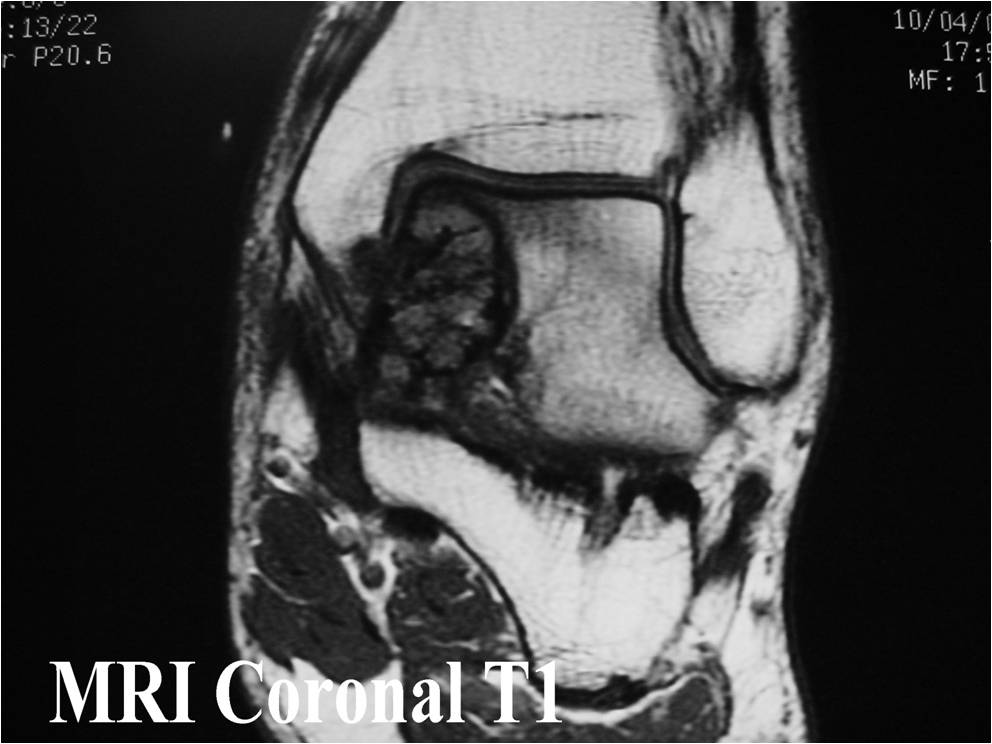

General Information Enchondroma is a benign indolent intramedullary hyaline cartilage neoplasm Accounts for 10% of all benign osseous tumors Limited growth, most lesions are less than 5 cm in maximal dimension Bones grow from a cartilaginous growth plate that...